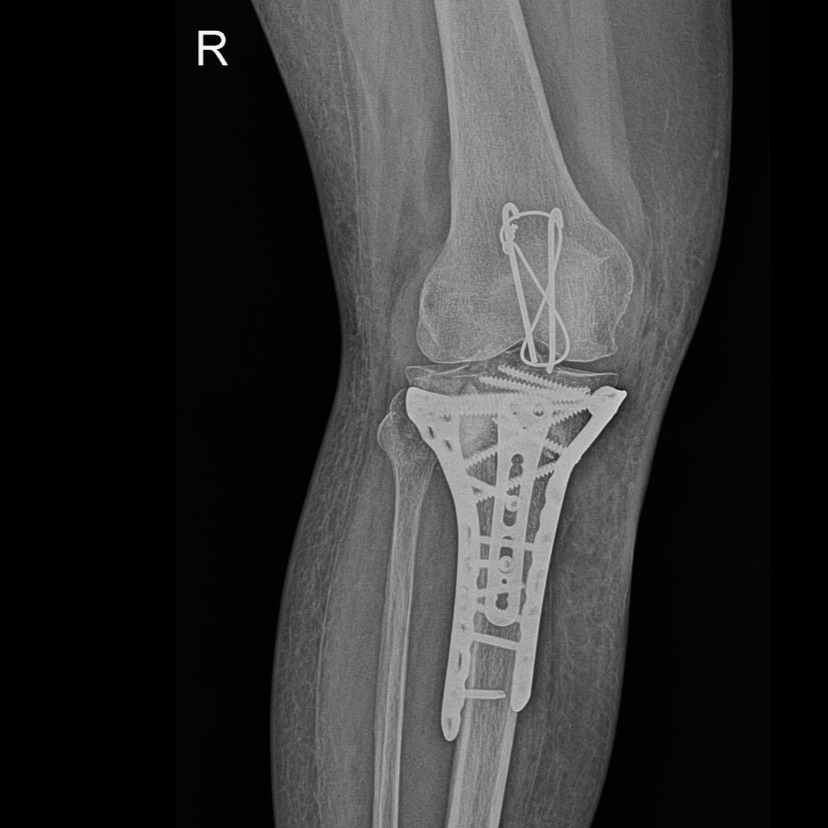

A 54 years old female sustained complex proximal tibia fracture following a fall at home in Rudrapur.

As She was operated by Dr Pankaj kumar in 2020 for Patella fracture on the same limb, happy with her last surgery and recovery, she travelled to Noida for surgery.

After anesthesia check up, she was operated with proximal tibia plates with bone grafting. Luckily her wound healed without any complication, she is able to stand painless and walk with stick after 3 months.

Proximal tibia fracture treatment is very challenging as fracture involves joint and skin condition delays surgery or healing.